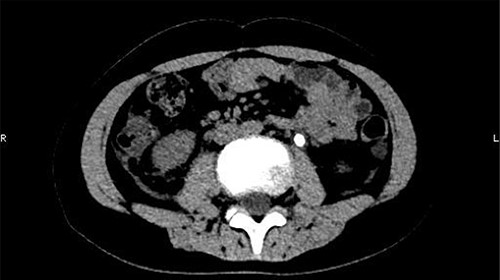

On 25 February, the patient complained of left back pain, nausea and vomiting. A further CT scan showed some irregular high-density shadows persisted in the left renal pelvis (Fig. 3) and an irregular high-density shadow was present in the left upper ureter (Fig. 4); furthermore, hydronephrosis was apparent in the left renal pelvis. There were no abnormalities in the bladder.

Some irregular high-density shadows persisted in the left renal pelvis, hydronephrosis was apparent in the left renal pelvis.

An irregular high-density shadow was present in the left upper ureter.